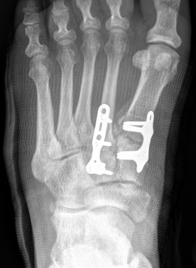

Screw versus bridge plating

- comparison of screw fixation versus bridge plating

- 60 ligamentous Lis Franc

- slightly better outcome scores at 2 years with bridge plate

- anatomic reduction: bridge plate 91%, screw 82%